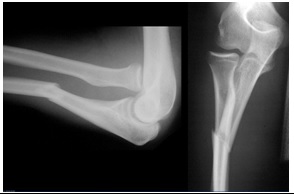

Seorang laki-laki, 20 tahun, dibawa ke IGD RS dengan keluhan nyeri dan bengkak pada lengan bawah kanannya akibat jatuh dari sepeda motor yang dikendarainya sejak 1 jam sebelum masuk RS. Pemeriksaan fisik menunjukkan bahwa pasien tidak mampu melakukan ekstensi ibu jari tangan kanan. Luka terbuka tidak ditemukan.

Apa diagnosis yang paling tepat untuk pasien ini?

| Fraktur tertutup diafisis ulna dextra + cedera nervus radialis dextra | |

| Fraktur tertutup Galeazzi dextra + cedera nervus interosseous anterior dextra | |

| Fraktur tertutup Galeazzi dextra + cedera nervus interosseous posterior dextra | |

| Fraktur tertutup Monteggia dextra + cedera nervus interosseous anterior dextra | |

| Fraktur tertutup Monteggia dextra + cedera nervus interosseous posterior dextra |